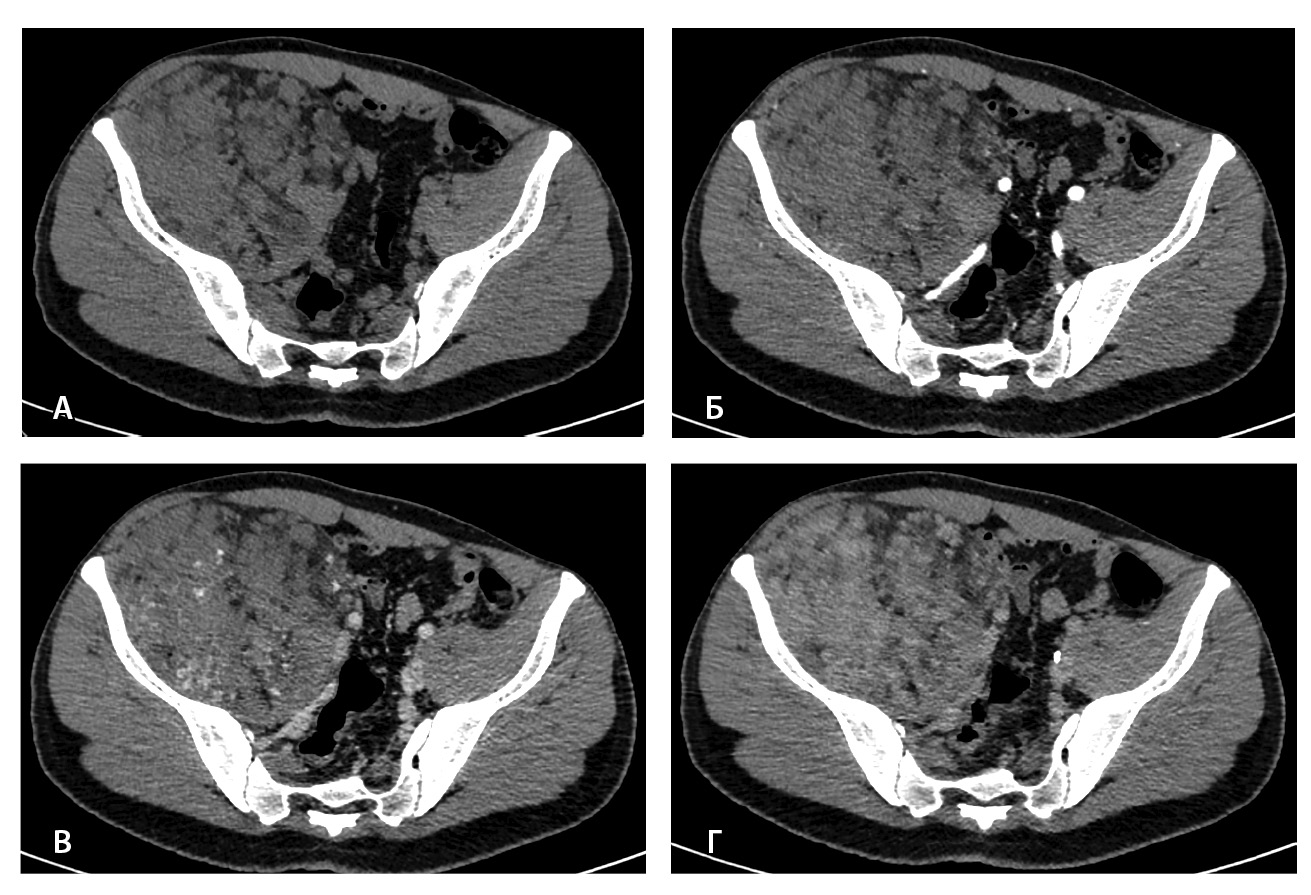

Рис. 2. Мультиспиральная компьютерная томография органов брюшной полости и забрюшинного пространства, режим костного окна. Кортикальный слой правой подвздошной кости прослеживается равномерно на всем протяжении, без признаков деструкции (стрелки)

Близкое расположение внутримышечных гемангиом к костям приводит к контактным изменениям последних. Методами лучевой диагностики выделяют три типа изменений костных структур – периостальные, кортикальные и медуллярные. Близость расположения образования к кости статически значимо коррелирует с любым типом костной реакции, а размер образования – лишь с медуллярным [14]. Агрессивный тип периостальной реакции и деструкция кортикального слоя могут быть ошибочно приняты за первичную опухоль кости [6, 15]. Однако эти изменения факультативны: так, в нашем исследовании никаких изменений костных структур отмечено не было.